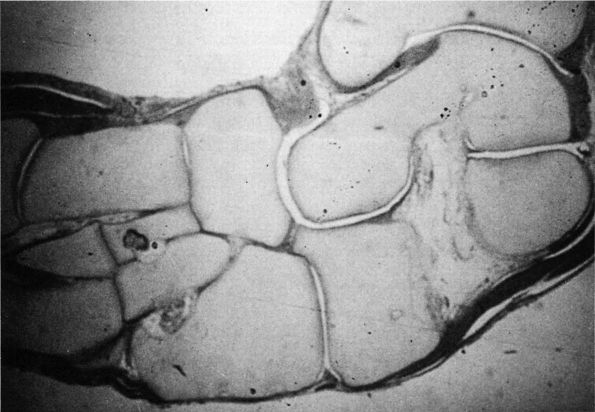

![]() |

FIGURE 20-20. Tarsal coalition. Fetal specimen demonstrating fibrous tarsal coalition between calcaneus and navicular.